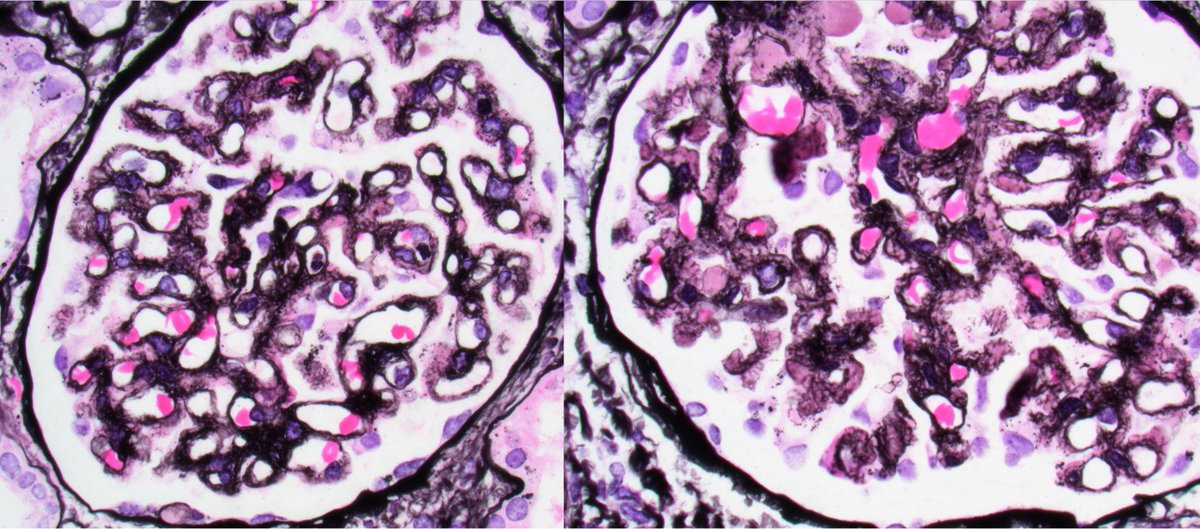

Teenager with nephrotic syndrome. Biopsy revealed unusual case of membranous nephropathy in a peds patient. PLA2R positive (IHC). PLA2R most common antigen in peds MN. EXT2 also common, SEMA3B less common. ( https://t.co/zEASwdQXIe)

#renalpath #pathsky #nephsky